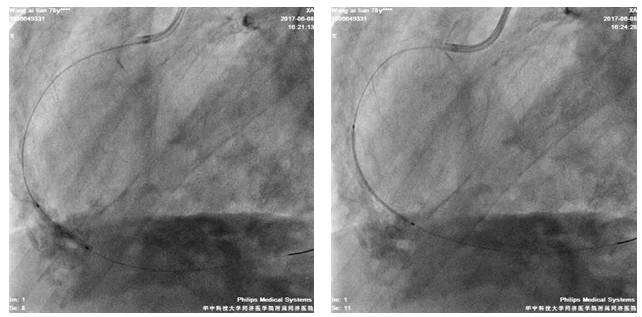

四日后,尝试左冠PCI术

股动脉路径

7F EBU3.5/GC

Runthrough NS,ASAHI SION,BMW导丝

2.5*20mm球囊扩张LAD10*12atm

先后与LAD远段-近段置入2.5*33mm、2.75*33mm、3.0*29mm DES支架,三支架串联